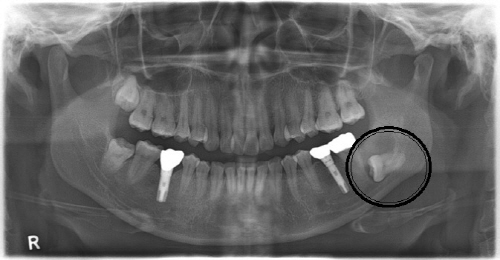

사랑니는 턱뼈가 작아진 현대인들의 구강 공간 부족으로 대부분 비뚫게 나거나 아예 턱뼈 속에 묻혀있는 경우가 많다.

보고에 의하면 완전히 잇몸뼈 안에 묻혀 있는 매복 사랑니의 약 3~23% 정도에서 물혹이나 종양 등 골치 아픈 합병증이 발생되는데, 턱뼈를 녹이고 상당히 크게 잠식할 때까지 증상이 없어 대부분 치과 치료 중 우연히 발견되거나 건강검진에서 발견되어 병원을 찾는 경우가 많다.

명훈 교수는 “사랑니와 물혹은 일반 치과에서 X-ray 검사로 간단히 진단할 수 있다. 20대에 사랑니가 나지 않았다고 해서 사랑니가 없다고 섣부르게 자가진단을 해서는 안 된다“고 조언했다.